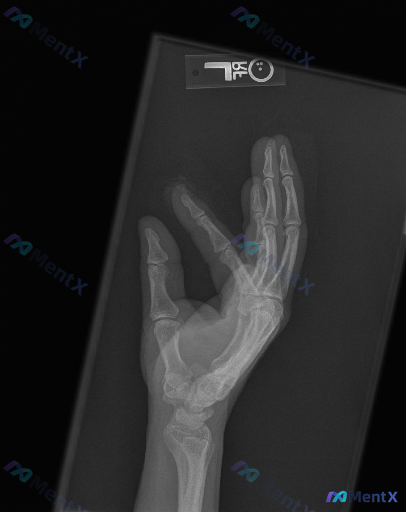

左手斜位X光片:结合临床诉求,影像层面该如何判断?

整理到一份左手斜位X光片的影像分析资料,结合临床有诉求的背景,想和大家讨论下这种情况的判读思路。 影像情况(基于分析报告整理): - 投照为左手斜位,部分掌骨指骨有重叠,符合该体位表现; - 可见远端桡尺骨、腕骨、掌骨及指骨,骨皮质连续性良好,骨小梁清晰,未见明确骨折线、皮质台阶或透亮线; - 各掌...